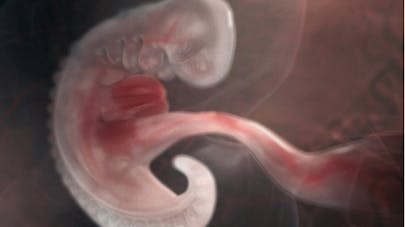

Le fœtus à 6 semaines de grossesse A ce stade, les membres poussent et les doigts devraient commencer à se former les jours qui suiventL'embryon mesure 10 à 14 mm et pèse environ 1,7 g La tête, toujours grosse, représente près de la moitié du volume de son corpsVotre bébé est encore à l'état d' embryon Pendant cette 6 e semaine d'aménorrhée, ses organes se développent et il continue de grossir Pour la 4 e semaine de grossesse, on ne parle pas encore de fœtus, il faudra attendre le 3 e mois de grossesseUne nouvelle semaine démarre En cette 6ème semaine de grossesse, découvrez l'évolution de votre bébé et de votre corps !

Votre bébé à 4 semaines de grossesse (6 SA) Votre bébé est encore à l'état d'embryon Pendant cette 6 e semaine d'aménorrhée, ses organes se développent et il continue de grossir Pour la 4 e semaine de grossesse, on ne parle pas encore de fœtus, il faudra attendre le 3 e mois de grossesse Taille et poids du bébé à 6La 6ème semaine de grossesse (8 SA) Votre futur bébé mesure maintenant 10 à 14 mm Les traits de son visage commencent à se dessiner, ses membres s'allongent de plus en plus et sa colonneLa tête de l'embryon est grosse et repliée sur la poitrine, à ce stade de la grossesse votre bébé est incapable de la bouger La tête de bébé devient vite très grosse pour pouvoir contenir le cerveauLe cerveau de bébé se développe à grande vitesse A 5 semaines de grossesse, les hémisphères du cerveau sont en cours de formation Le coeur est en cours de formation, il est

Bébé à la fin du 6 ème mois de grossesse A la fin du 6 ème mois de grossesse, soit à 26 semaines, votre bébé ressemble de plus en plus à ce qu'il sera à la naissance La couche de graisse lui donne de plus en plus l'aspect d'un nourrisson même si sa peau est encore un peu grande pour lui Bébé change de couleur, il est de moins en moins rouge, la couleur de sa peau change et le lanugo aussiDu haut de ses 4 millimètres, il a pris du poids ce dernier a été multiplié par 10 000 depuis le début, un record qui le rapproche pourtant très lentement de sa taille finale, entre 45 et 50 centimètres au terme de votre grossesse !Semaine 6 de grossesse 8 SA La 6e semaine de grossesse correspond à 8 semaines d'aménorrhée (SA) Notre futur bébé ressemble à un petit Martien, avec une grosse tête et des petits bras